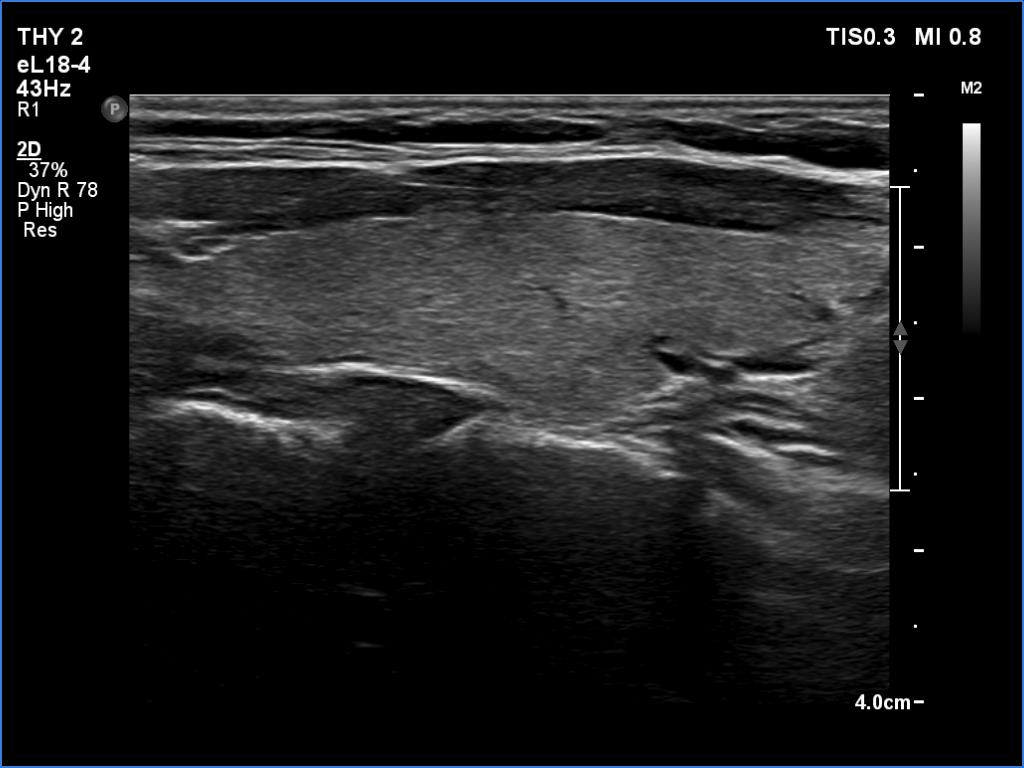

Follow-up 6 months after the first visit (3rd row of images):

Clinical presentation: The patient had no complaints.

Palpation: no abnormality.

Laboratory tests: TSH 2.06 mIU/L, FT4 13.3 pM/L, CRP 0.3 mg/L.

Ultrasonography: The pattern of the entire thyroid became almost completely normal. Only small hypoechoic areas were observed.

Suggestion: TSH in six months, in the event of pregnancy at once.

Follow-up 5 years later (3rd row of images):

Clinical presentation: Six months after the previous visit the patient became pregnant. The TSH was 5.91 mIU/L at the 5th gestational weeks. Replacement therapy was given which was ceased after delivery. The patient was free of complaints and the TSH was in the normal range, even during a next pregnancy 2 years later. Recently, a few weeks after COVID-19 infection, she noticed tenderness in the right side of the neck.

Laboratory tests: TSH 1.72 mIU/L, CRP 3.5 mg/L.

Ultrasonography: The thyroid was intact.